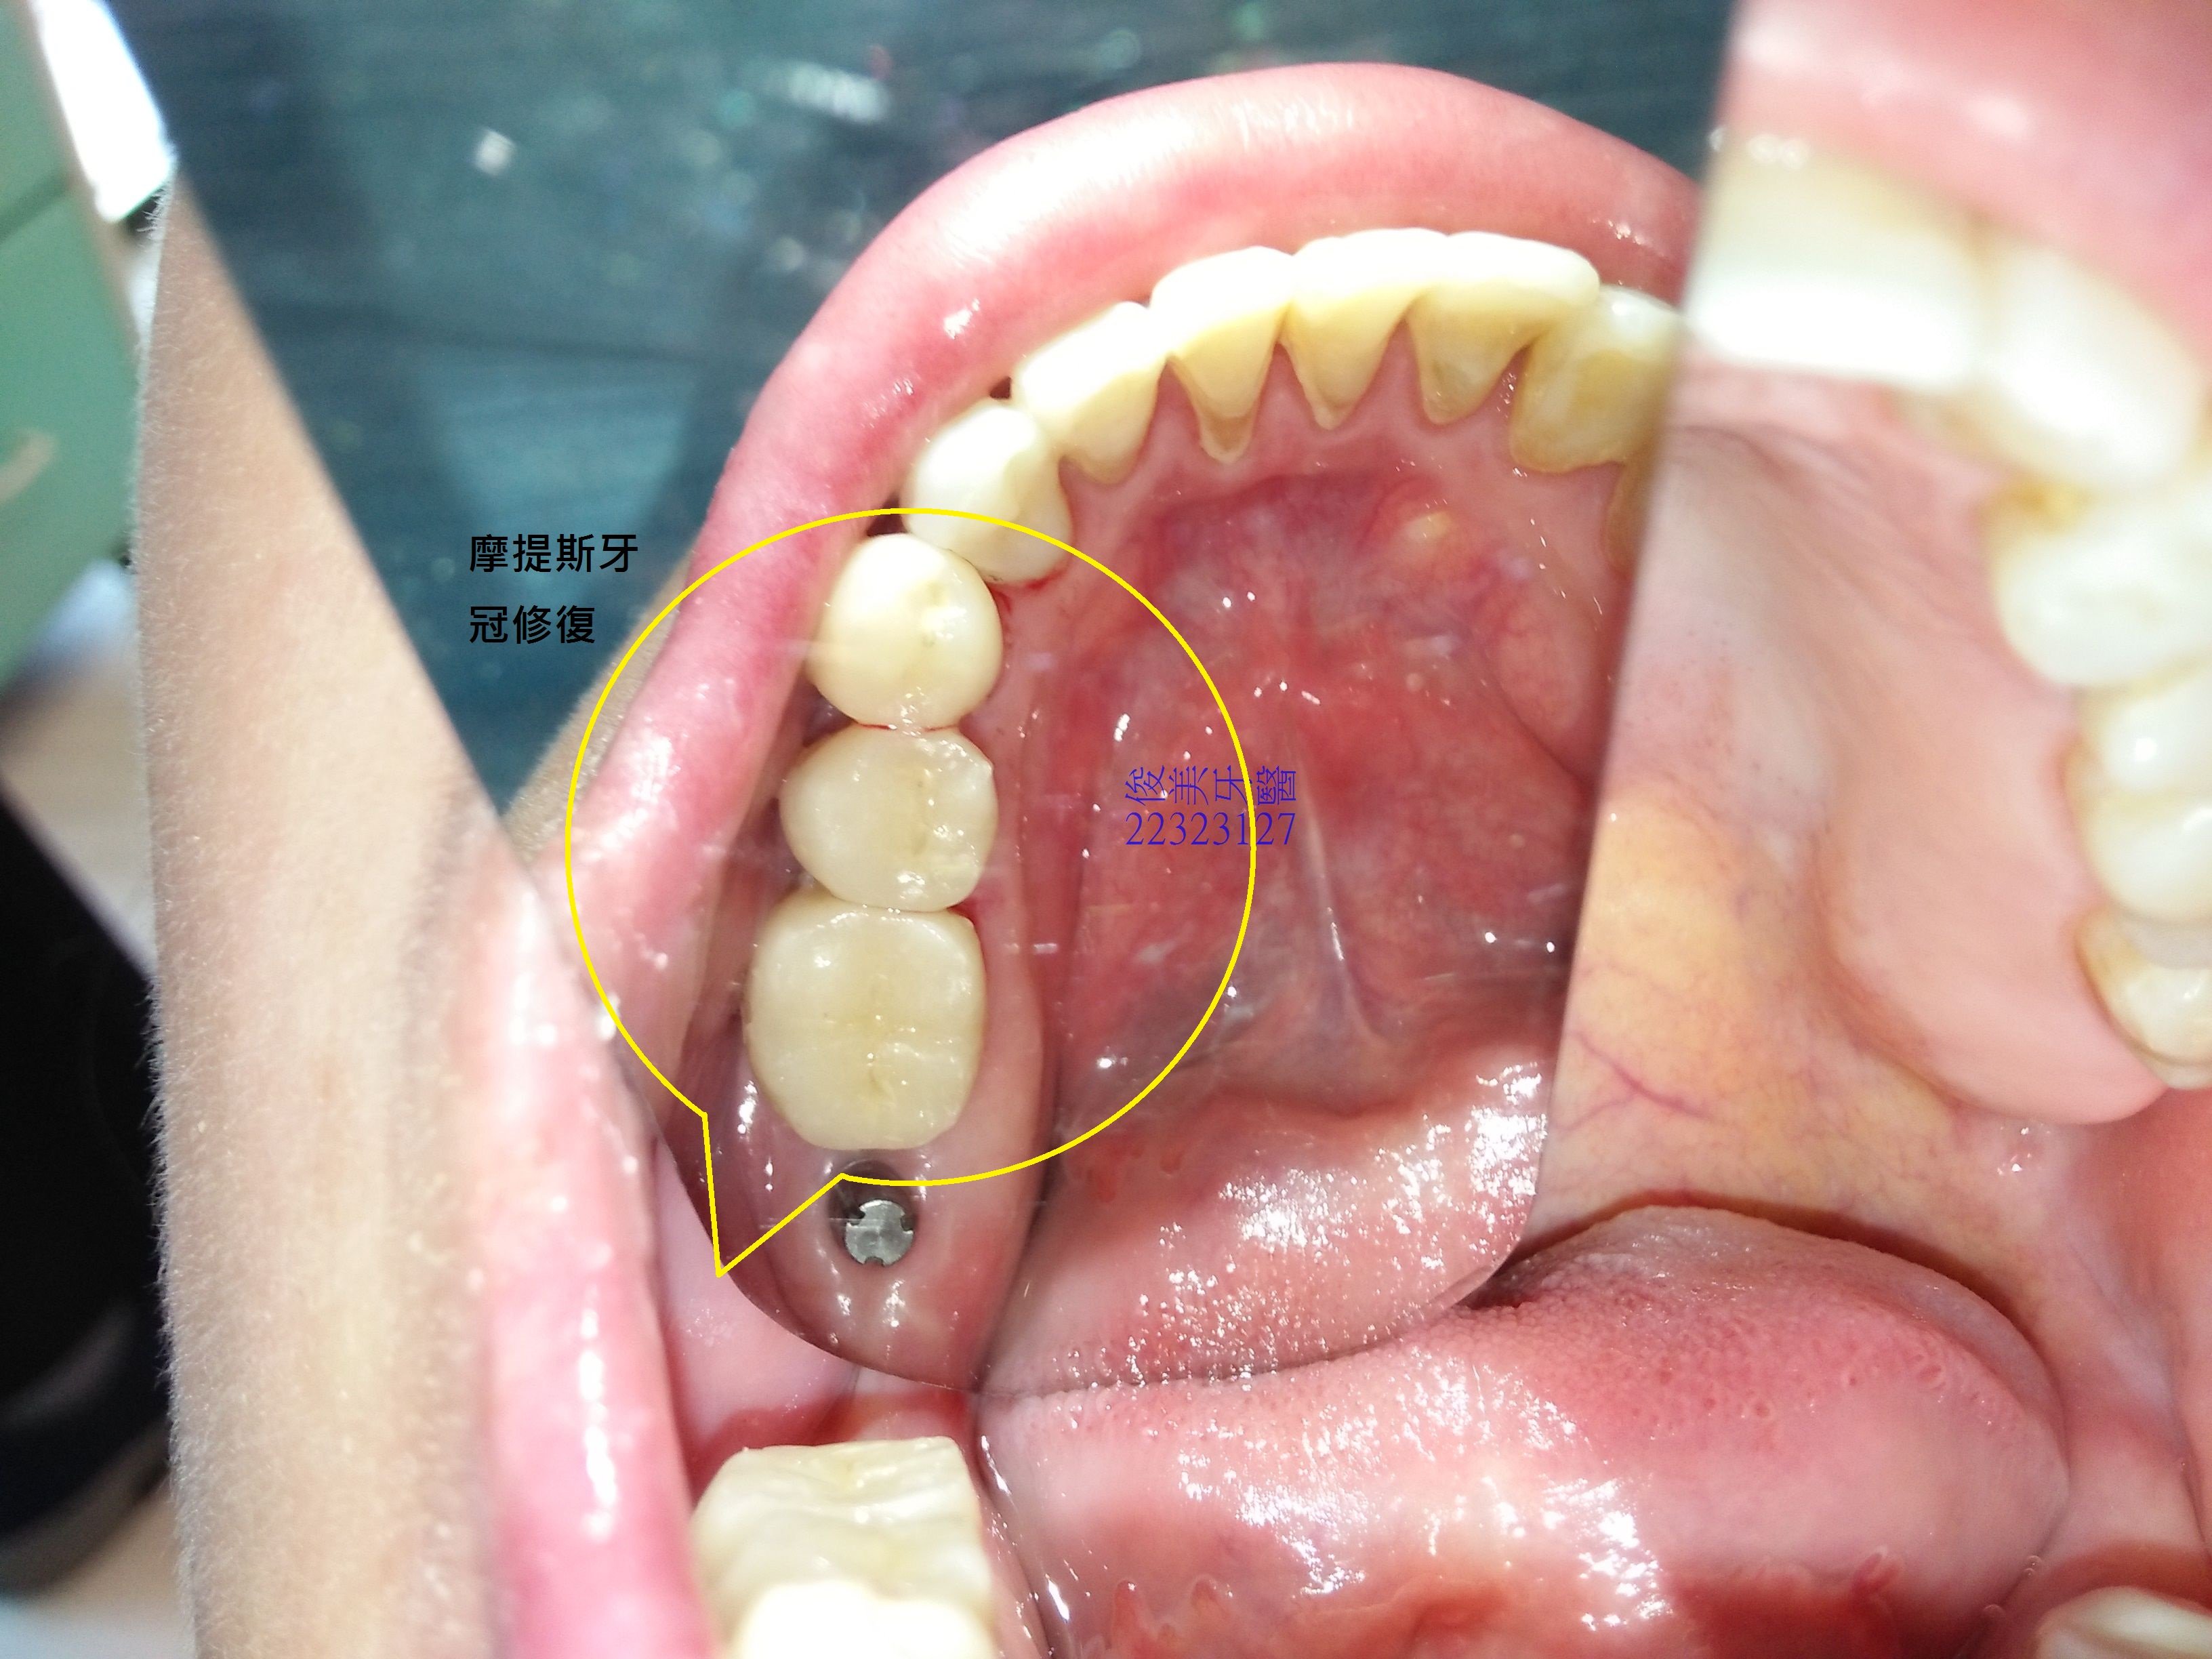

榫接式人工牙冠案例11

患者因多年前做過矯正,但當時因覺牙齒太暴,所以拔了牙做矯正,多年下來,牙齒都有過度磨損的現象,因此在醫師的評估後,決定採摩提斯牙冠來修復,避免破壞自已所剩無幾的琺瑯質,並先用臨時的來適應高度,在適應後即印模.....

不需修磨過多齒質,更加不用傷害牙齒寶貴的神經..

全瓷材質,達到最少破壞、最大修復效果,術後不敏感,可以使用牙線清潔。

至於缺牙採人工植牙修復,增加患者的支柱牙,分散牙齒全體的咬合力量,延長牙齒的壽命。